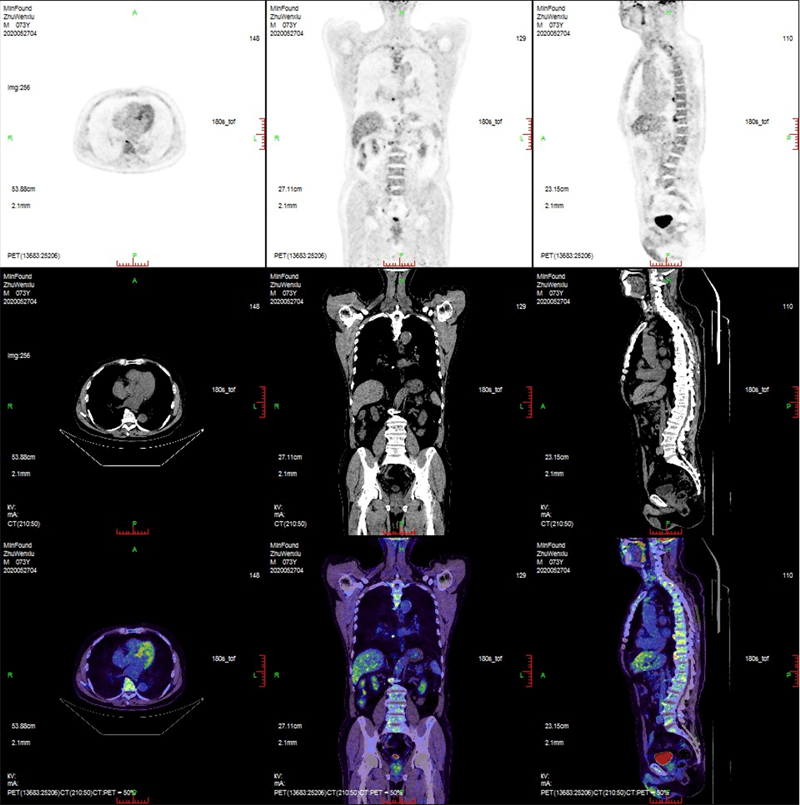

Clinical Gallery